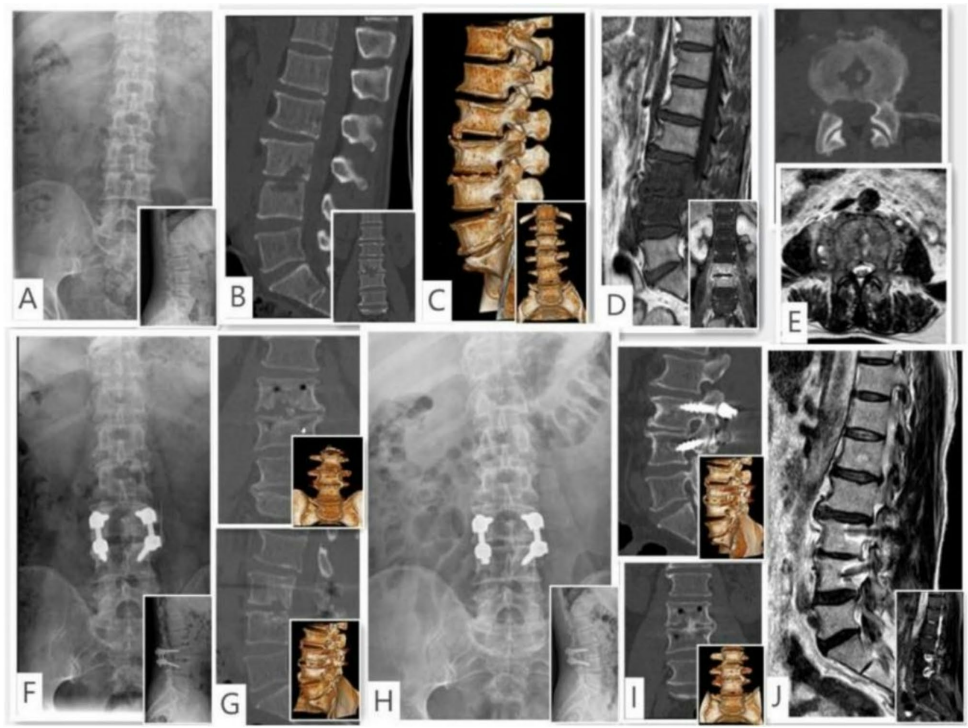

【临床疗效】术后24个月随访显示:VAS评分降幅达94.4%,JOA评分改善幅度93.3%,所有神经功能缺损患者恢复至ASIA E级。影像学参数中,Cobb角从术前22.0±5.94°矫正至10.37±2.02°(P<0.05),91.11%病例达到BridwellⅠ-Ⅱ级骨融合。典型病例影像显示: